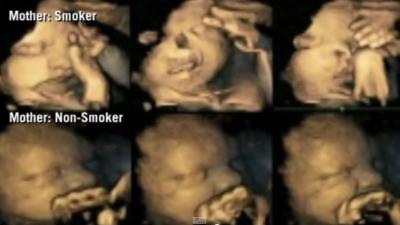

Zwangere vrouwen die roken zullen bij het zien van deze beelden mogelijk direct hun rookwaar verbannen.

Als geen enkele vrouw tijdens de zwangerschap zou roken, zou de sterfte rond de geboorte en een laag geboortegewicht met 10 procent kunnen dalen.

Zwangere vrouwen die roken tijdens hun zwangerschap krijgen van het UMCG hulp aangeboden bij het stoppen met roken. Noord-Nederland heeft het hoogste percentage

Het percentage vrouwen dat rookt tijdens de zwangerschap is de laatste jaren niet afgenomen. Onder hoogopgeleide zwangeren is het percentage rokers tussen 2010